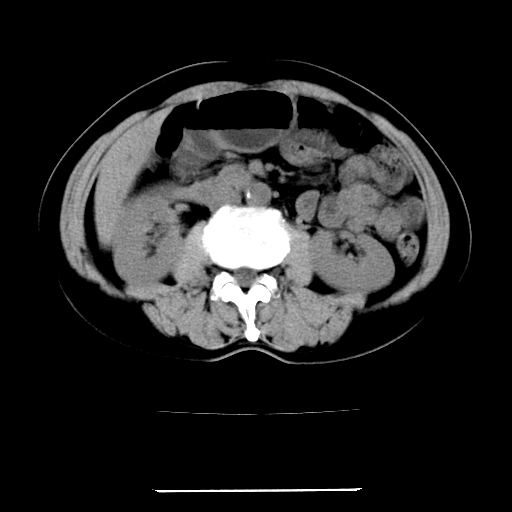

标题: CT22301:女,67岁,上腹部疼痛一周伴皮肤黄染,无发热。 [打印本页]

女,67岁,上腹部疼痛一周伴皮肤黄染,无发热。

1、肝门高密度影下层面和胰头层面可见轻度胆管扩张,而静脉和延迟期均未见扫描完胰头,不能完全排除胰头占位。2、肝门部高密度影,考虑钙化或结石。